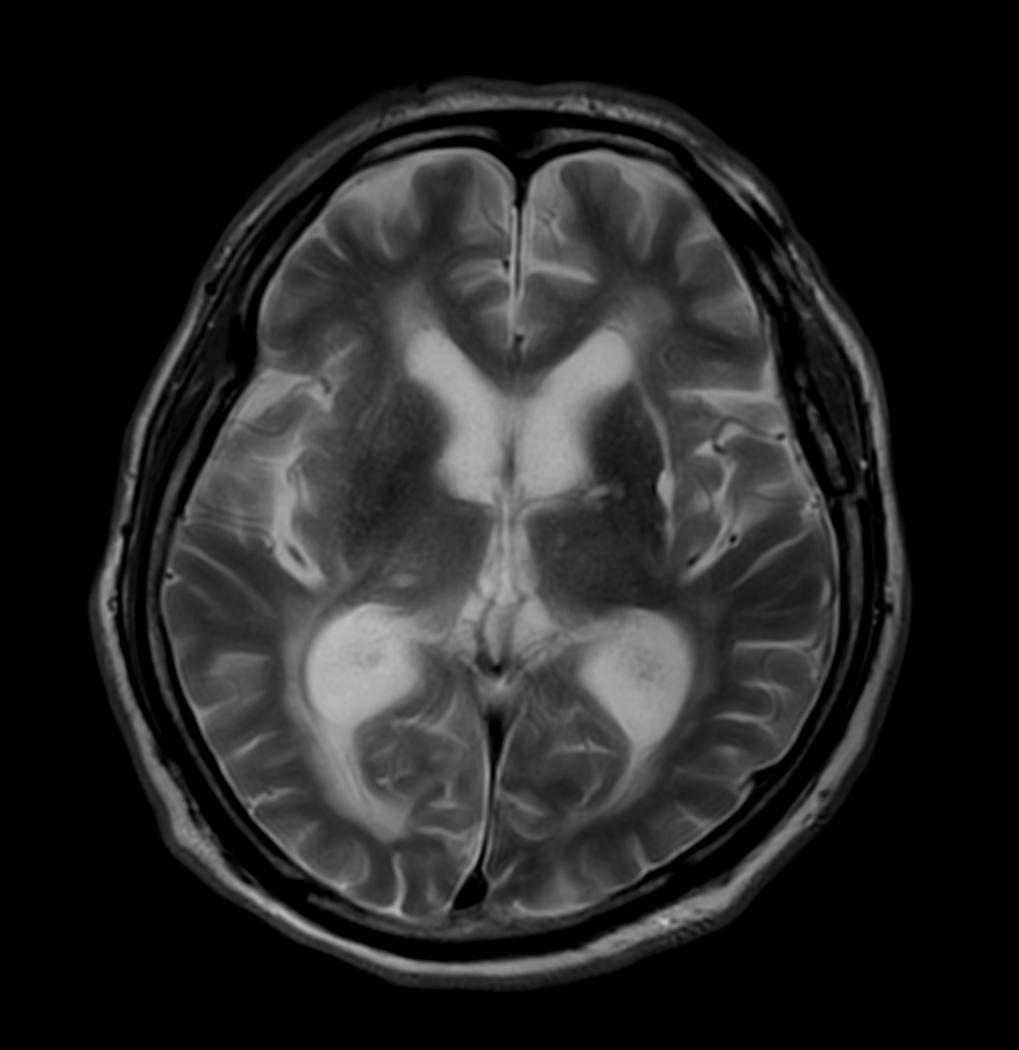

T2w TSE - MultiVane XD